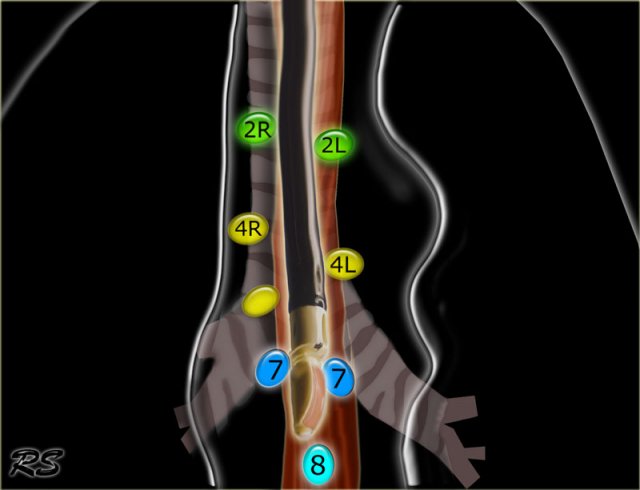

Superior Mediastinal Nodes 2-4

2R.Upper Paratracheal

2R nodes extend to the left lateral border of the trachea.

From upper border of manubrium to the intersection of caudal margin of innominate (left brachiocephalic) vein with the trachea.

2L.Upper Paratracheal

From the upper border of manubrium to the superior border of aortic arch.

2L nodes are located to the left of the left lateral border of the trachea.

4R.Lower Paratracheal

From the intersection of the caudal margin of innominate (left brachiocephalic) vein with the trachea to the lower border of the azygos vein.

4R nodes extend from the right to the left lateral border of the trachea.

4L.Lower Paratracheal

From the upper margin of the aortic arch to the upper rim of the left main pulmonary artery.

Inferior Mediastinal Nodes 7-9

7.Subcarinal

8. Paraesophageal

Nodes below carina.

7. Subcarinal nodes

These nodes are located caudally to the carina of the trachea, but are not associated with the lower lobe bronchi or arteries within the lung.

On the right they extend caudally to the lower border of the bronchus intermedius.

On the left they extend caudally to the upper border of the lower lobe bronchus.

8 Paraesophageal nodes

These nodes are below the carinal nodes and extend caudally to the diafragm.